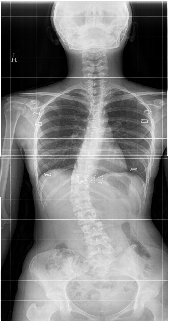

±Á°í Èִ ôÃßȯÀÚ 10´ë¿©¼º 'ÃÖ´ë'

È£¸£¸ó ÀÌ»ó µîÀ¸·Î ôÃß°¡ ¿·À̳ª ¾Õ¡¤µÚ·Î ÈÖ´Â 'ôÃß±ÁÀ½Áõ' ȯÀÚ°¡ ¿©¼ºÀÌ ³²¼ºº¸´Ù 1.9¹è³ª ¸¹Àº °ÍÀ¸·Î ³ªÅ¸³µ´Ù. 2014-02-23 10:25:09